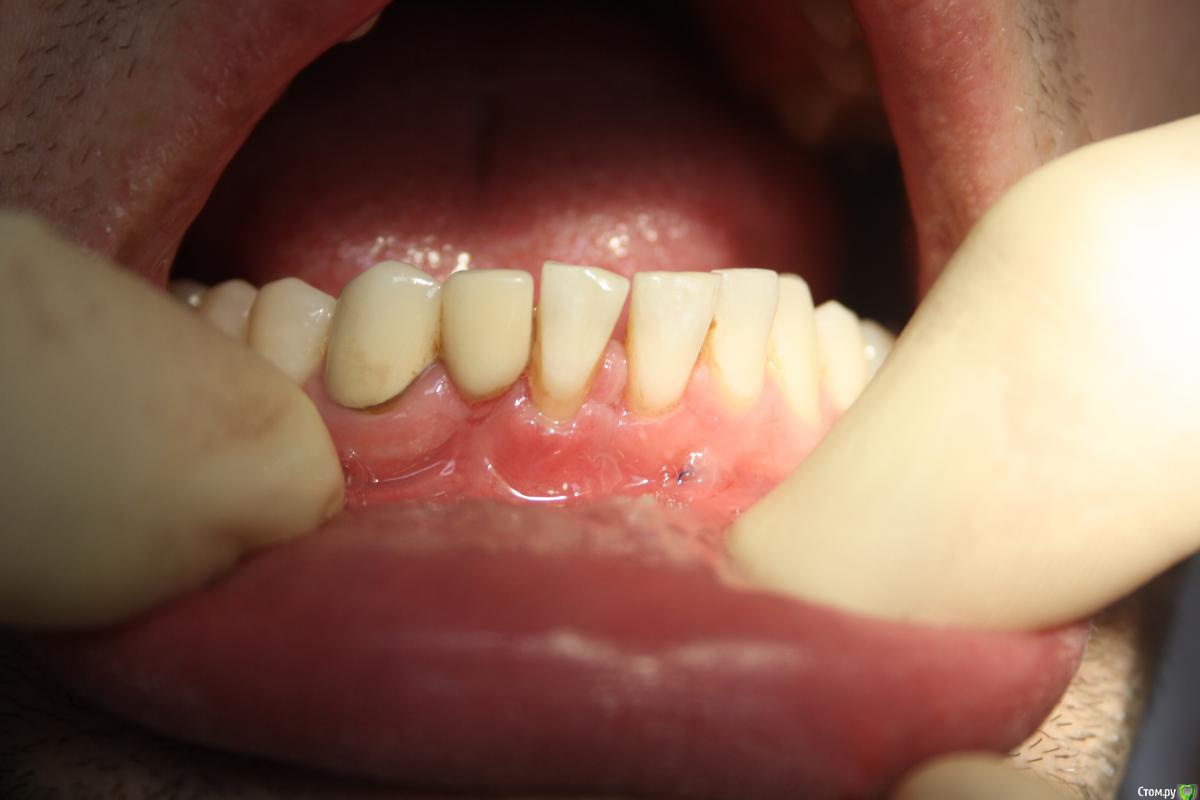

Zubnik7 Опубликовано 4 октября, 2016 Поделиться Опубликовано 4 октября, 2016 Планирую закр.рецессию на 41 зубе,сначала планировал пересадку субэпит.транспланта и смещение коронально,но 42 зуб отсутсвует,может просто латеральный лоскут сместить с 42?как переворачивать фото не разобрался Ссылка на комментарий

kamranchick Опубликовано 4 октября, 2016 Поделиться Опубликовано 4 октября, 2016 Планирую закр.рецессию на 41 зубе,сначала планировал пересадку субэпит.транспланта и смещение коронально,но 42 зуб отсутсвует,может просто латеральный лоскут сместить с 42?как переворачивать фото не разобралсяначать с гигиены сначала, а потом можно уже проанализировать, думаю десна поднимется колониально и сможете сделать туннель Ссылка на комментарий

Nazim_NV86 Опубликовано 5 октября, 2016 Поделиться Опубликовано 5 октября, 2016 Сначала увеличьте ЗПД пересадкой ССТ. Желательно запитать его на 3-4мм влево и вправо. Откинуться лоскутом. Тоннелем вы много не получите. Мобилизовать придётся. Ссылка на комментарий

Zubnik7 Опубликовано 5 октября, 2016 Автор Поделиться Опубликовано 5 октября, 2016 Травма механическая,42 зуб отсутсвует поэтому,я тоже склоняюсь к пересадки ССТ Ссылка на комментарий